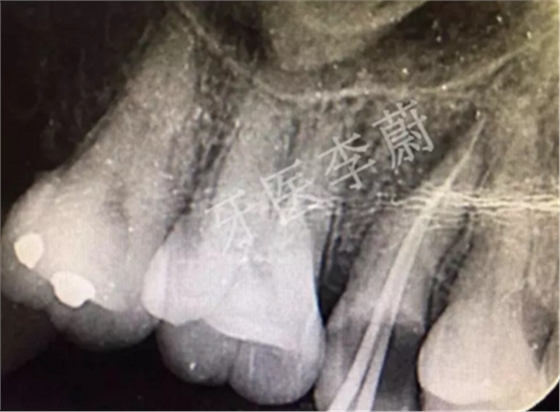

15牙根管充填術(shù)后X牙片

15牙根管預(yù)備試尖片